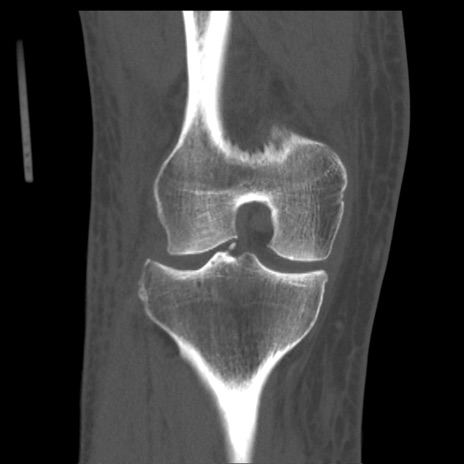

症例28 右膝関節CT(冠状断像)

右膝関節CT